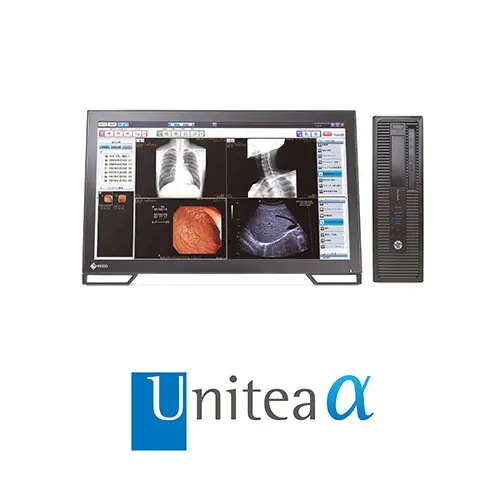

| 画像診断ワークステーション REGIUS Unitea |

「Unitea α」の詳細を見る |

『Unitea α』とのワンクリック連携

「Uniteaα」で表示中の患者情報を、超音波診断装置からワンクリックで取得することでシンプルなワークフローを実現します。